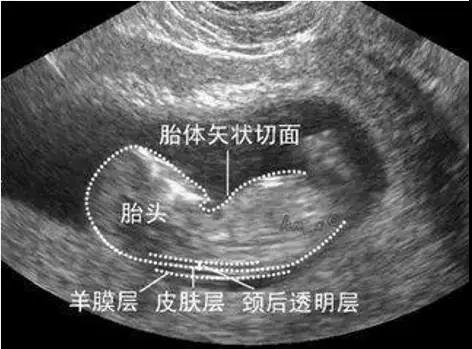

NT即 nuchal translucency 的缩写,它指的是胎儿的 “ 颈项透明层 ”,也就是指胎儿颈椎水平冠状切面皮肤至皮下组织之间的最大厚度,其实就是指胎儿颈后部皮下组织内液体积聚的厚度。

通常用的判断指标:妊娠11-14周+6天时,NT ≥ 2.5毫米视为异常。